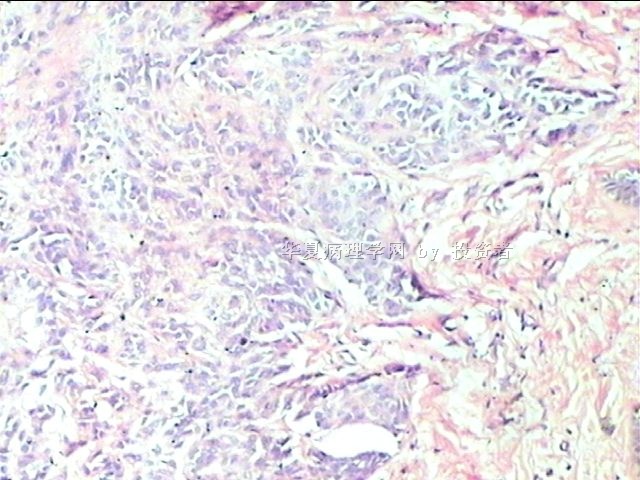

B1634求助皮肤赘生物肿瘤类型

姓    名: ××× 性别:  女 年龄:  25

标本名称: 尾骨下端皮肤赘生物

简要病史:  皮肤赘生物10年余

肉眼检查:  体积1×0.5×0.3cm

×参考诊断

皮内痣

隐约中见似皮内痣。

皮内痣,披着神秘的面纱。

染色太淡,看不清楚。

谢谢各位老师,皮内痣,学习了!

皮内痣可能